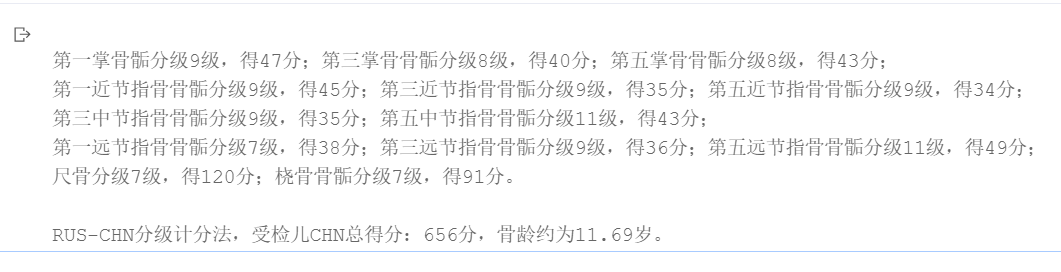

骨龄3